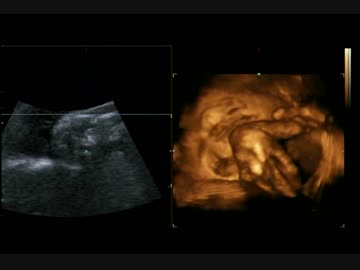

【エコー】赤ちゃん(33週)終